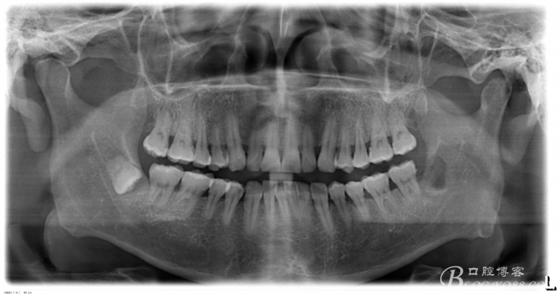

一、術(shù)前CBCT影像資料

圖13.術(shù)后的全景片影像